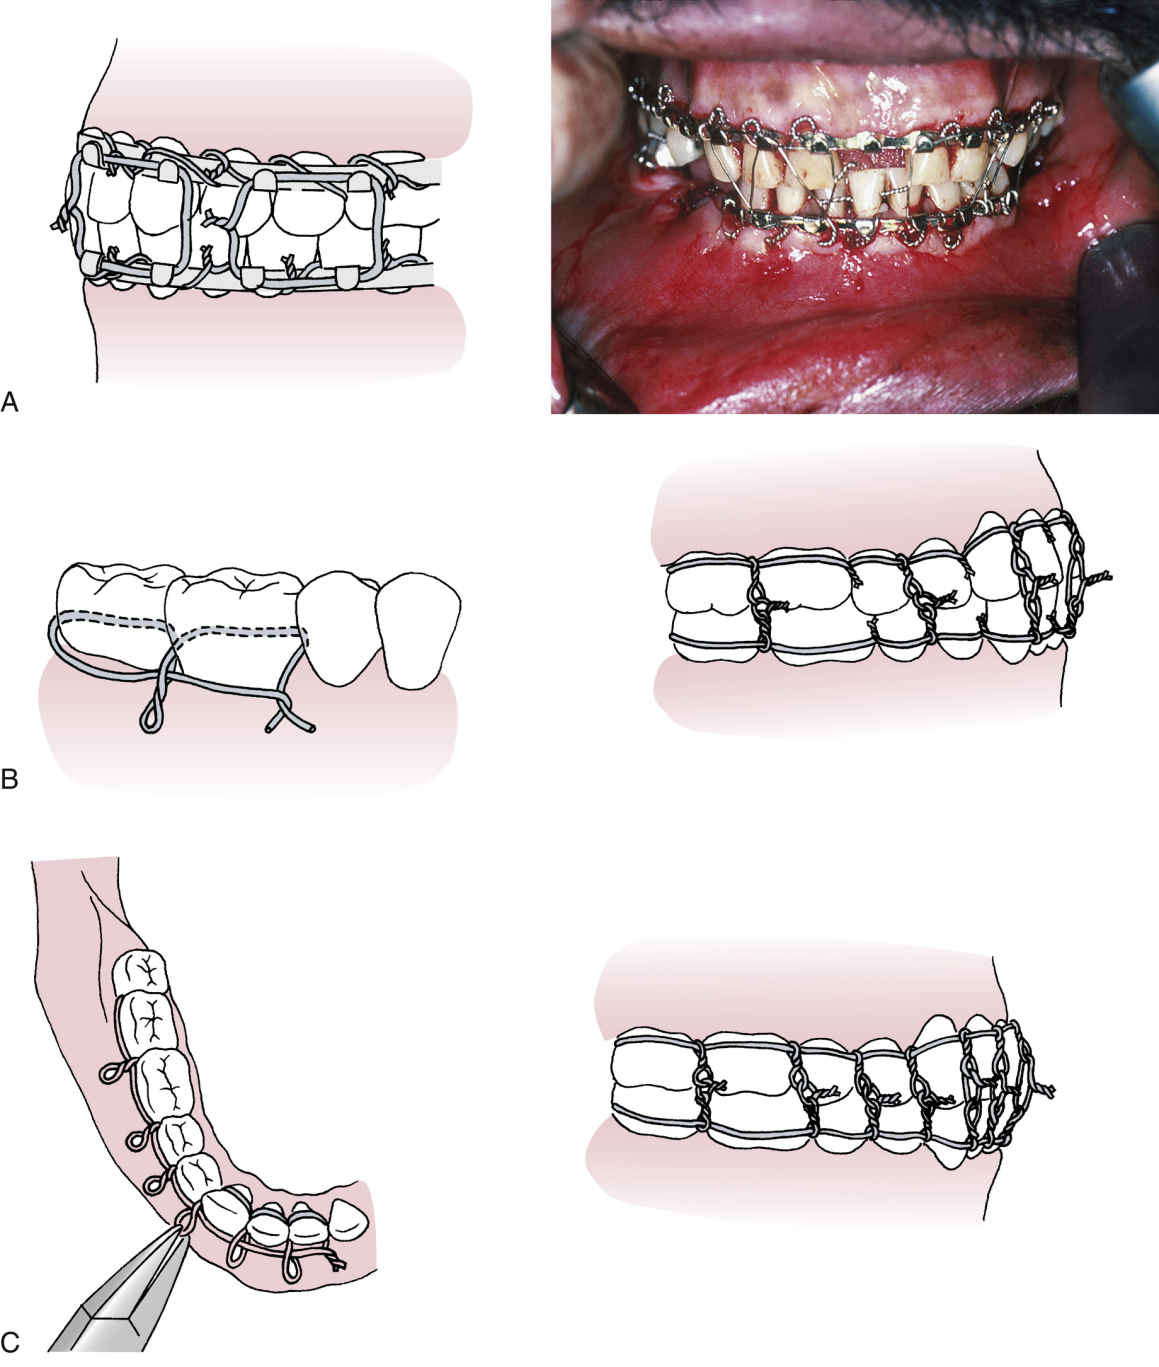

Wiring Techniques In Maxillofacial Surgery The oral and maxillofacial region has a complex regional anatomy including hard and soft tissues. Mmf has long been used as a fixation technique for reduction of fractures by wiring or banding the maxilla and mandible to reduce the fracture. This document discusses various techniques for closed reduction of mandibular fractures including direct and indirect interdental wiring methods like essig's, gilmer's,. The oral and maxillofacial region has a complex regional anatomy including hard and soft tissues. The ao/asif's impact on maxillofacial surgery is evident through its emphasis on internal fixation since 1958,. Different plating systems and wiring techniques make the management of these maxillofacial fractures predictable with high.

Department of Oral & Maxillofacial Surgery conducting on Wiring Techniques In Maxillofacial Surgery Mmf has long been used as a fixation technique for reduction of fractures by wiring or banding the maxilla and mandible to reduce the fracture. The oral and maxillofacial region has a complex regional anatomy including hard and soft tissues. This document discusses various techniques for closed reduction of mandibular fractures including direct and indirect interdental wiring methods like essig's,. Wiring Techniques In Maxillofacial Surgery.

Tight Placement of Erich Arch Bar While Avoiding Wire Fatigue Failure Wiring Techniques In Maxillofacial Surgery This document discusses various techniques for closed reduction of mandibular fractures including direct and indirect interdental wiring methods like essig's, gilmer's,. Different plating systems and wiring techniques make the management of these maxillofacial fractures predictable with high. The oral and maxillofacial region has a complex regional anatomy including hard and soft tissues. The ao/asif's impact on maxillofacial surgery is evident. Wiring Techniques In Maxillofacial Surgery.

Wiring techniques in maxillofacial surgery Wiring Techniques In Maxillofacial Surgery This document discusses various techniques for closed reduction of mandibular fractures including direct and indirect interdental wiring methods like essig's, gilmer's,. The ao/asif's impact on maxillofacial surgery is evident through its emphasis on internal fixation since 1958,. Mmf has long been used as a fixation technique for reduction of fractures by wiring or banding the maxilla and mandible to reduce. Wiring Techniques In Maxillofacial Surgery.

SOLUTION Wiring in oral and maxillofacial surgery Studypool Wiring Techniques In Maxillofacial Surgery Mmf has long been used as a fixation technique for reduction of fractures by wiring or banding the maxilla and mandible to reduce the fracture. The oral and maxillofacial region has a complex regional anatomy including hard and soft tissues. Different plating systems and wiring techniques make the management of these maxillofacial fractures predictable with high. The ao/asif's impact on. Wiring Techniques In Maxillofacial Surgery.

Wiring techniques in maxillofacial surgery Wiring Techniques In Maxillofacial Surgery This document discusses various techniques for closed reduction of mandibular fractures including direct and indirect interdental wiring methods like essig's, gilmer's,. The ao/asif's impact on maxillofacial surgery is evident through its emphasis on internal fixation since 1958,. Different plating systems and wiring techniques make the management of these maxillofacial fractures predictable with high. Mmf has long been used as a. Wiring Techniques In Maxillofacial Surgery.

Wiring techniques in maxillofacial surgery Wiring Techniques In Maxillofacial Surgery Mmf has long been used as a fixation technique for reduction of fractures by wiring or banding the maxilla and mandible to reduce the fracture. This document discusses various techniques for closed reduction of mandibular fractures including direct and indirect interdental wiring methods like essig's, gilmer's,. The oral and maxillofacial region has a complex regional anatomy including hard and soft. Wiring Techniques In Maxillofacial Surgery.